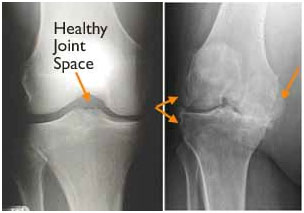

• (Left) In this x-ray of a normal knee, the space between the bones indicates healthy cartilage (arrow). (Right) This x-ray of an arthritic knee shows severe loss of joint space and bone spurs (arrows).